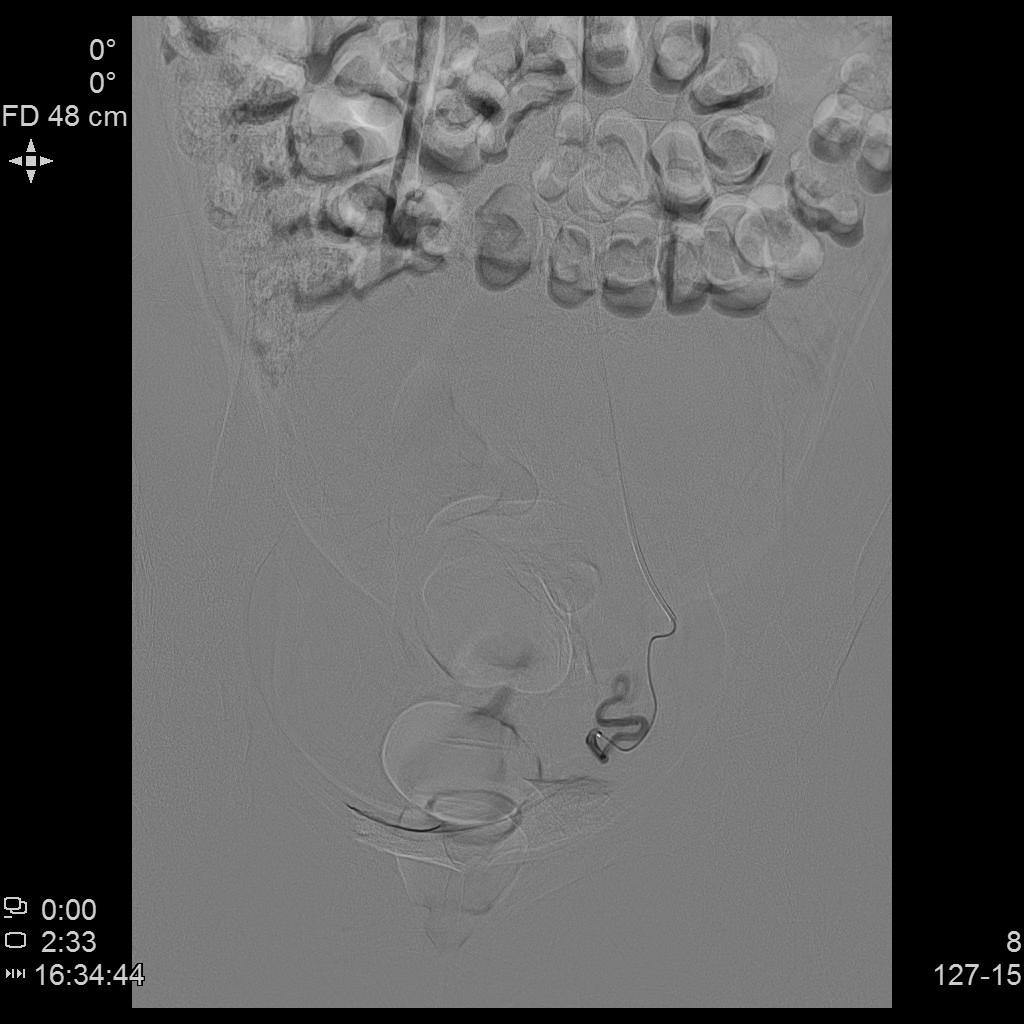

- 经桡动脉入路插管,微导管进一步超选插管右侧子宫动脉主干造影确认位置,随后行动脉栓塞治疗。

- 微导管进一步超选插管左侧子宫动脉主干造影确认位置,随后行动脉栓塞治疗。

- 术后桡动脉止血器压迫止血8小时,患者术后无需长时间卧床、下肢制动,舒适度大大提升,利于术后快速康复。